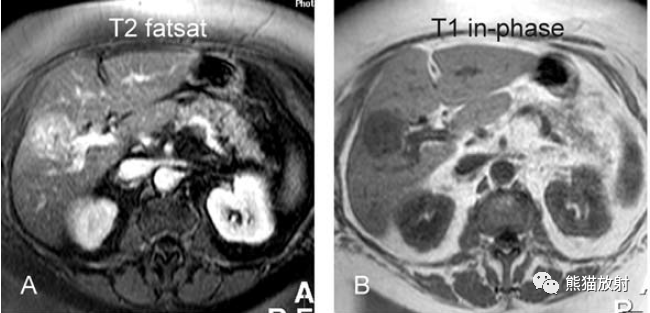

T2壓脂(T2 fatsat):膽囊窩內膽囊癌病變較肝臟為高信號,病變頂部向肝內擴展;

T1同相位(T1 in-phase):膽囊癌病變較肝臟為低信號;

膽囊癌。A~D圖:上方層面,表現如上所述,形成腫物侵及肝臟。E、F圖:下方層面示膽囊壁不規則增厚,明顯不均質強化。